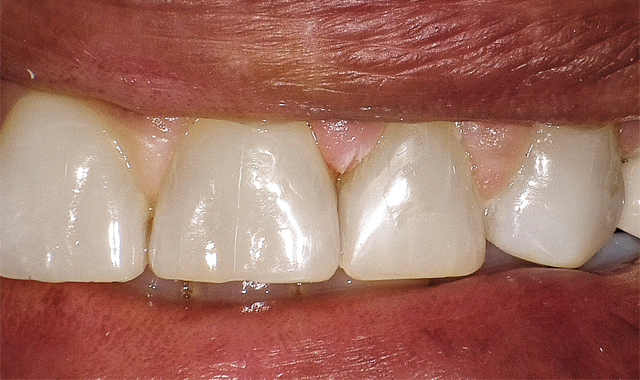

After placement of a bulk fill low stress flowable and again appropriate light curing, the final 2 mm of warmed A2 G-ænial Sculpt was placed in one bulk fill manner. After finishing and polishing, the above restoration truly maximizes tooth preservation (Fig. 3).

After finish and polishing, this restoration truly maximizes tooth preservation.